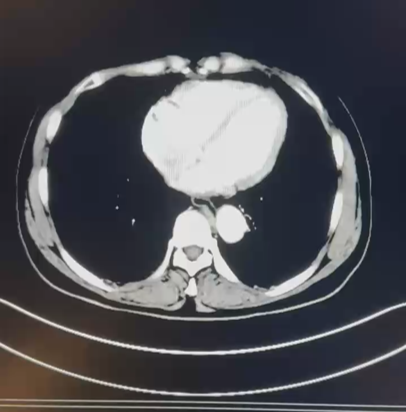

2024.1检查报告

CT 检查报告

1.左肺动脉主干及分支、右下肺动脉分支多发肺栓塞;

2.下腔静脉、右肾静脉及其属支、左肾静脉及左侧髂总静脉多发血检形成,请结合临床。

3.双肺散在炎症,双侧胸膜增厚;

4.右肾大片状低强化灶,请结合临床。

日期:2024.1.10